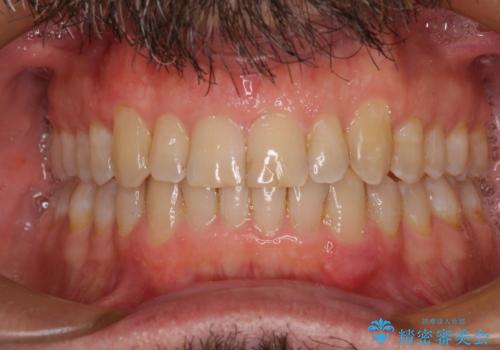

【モニター】前歯のデコボコを治したい インビザライン矯正治療

- 前歯のデコボコを気にして来院された患者様です。

インビザラインでもワイヤー装置でも対応可能でしたが、仕事の都合で来院回数を減らしたいとのことでインビザラインによる矯正治療を選択されました。

著しく咬合力が強いため、奥歯がしっかりと噛めずに治療が長引くことが懸念されました。

1セット目のインビザラインを使用した際には左右ともに大臼歯が咬み合っていなかったのですが、2セット目できっちりと仕上げることができました。